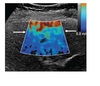

What does this image demonstrate?

A

Colour maps/ Contrast with static Elastography

In terms of stress testing, which colour indicates what with static Elastography?

Blue green colour indicates stiffer/harder tissue and red is softer